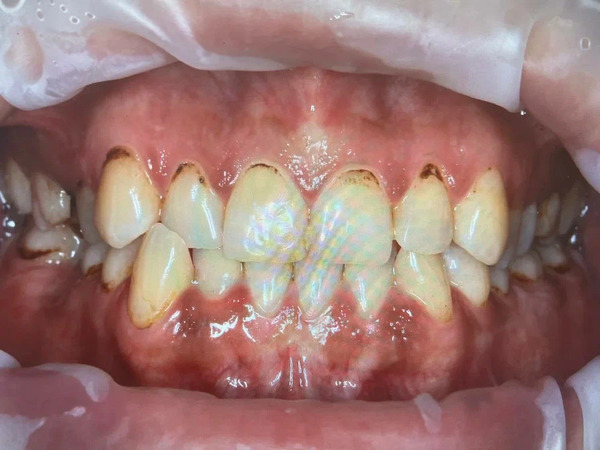

Для курильщиков характерно, что потемнение зубной эмали и кариес образуются в первую очередь не с наружной, а с внутренней (язычной или нёбной) стороны зубов. Там, где они больше соприкасаются со слизистой и происходит основное вдыхание дыма.

Локализация тёмного налёта у курильщика в пришеечной и межзубной зонах. Впоследствии именно здесь чаще всего образуется кариес — на фото его можно увидеть на правом верхнем клыке и левой нижней шестёрке.